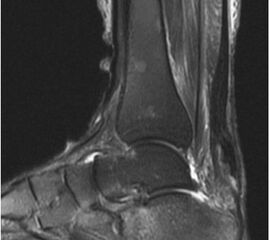

Der geübte Untersucher kann anhand des seitlichen Röntgenbildes die Diagnose einer Achillessehnenruptur stellen. Die Konturen des Kager-Dreiecks – gebildet von der ventralen Begrenzung der Achillessehne, der posterioren Tibiakante und der kranialen Kalkaneuskortikalis – verstreichen im Rupturfall (Kager 1939). Die MRT- Diagnostik spielt für die Primärdiagnostik der frischen Achillessehnenruptur eine untergeordnete Rolle und ist im Normalfall nicht notwendig. Anders verhält es sich bei den chronischen Rupturen. Hier ist die MRT ein wichtiges Diagnostikum insbesondere in Hinblick auf die Beurteilung der Sehnen- und Muskeldegeneration (Abb. 6).

Abbildung 6

Neben der strukturellen Wiederherstellung der Sehne ist die funktionelle Beurteilung des Muskels von entscheidender Bedeutung. Ist es bereits zu einer Degeneration der Muskeln gekommen, kann ein gutes funktionelles Ergebnis, trotz subtiler Sehnenrekonstruktion, nicht erreicht werden. Die Arbeitsgruppe um Hoffmann et al. 13 konnte in ihrer Arbeit zeigen, das es - ähnlich wie bei Patienten mit chronischen Supraspinatusrupturen - zu fettigen Degenerationen und Ödemen der Muskulatur kommt, die im MRT nachweisbar sind. Wir empfehlen die MRT- Untersuchung des gesamten Unterschenkels und nicht nur die rupturnahen Bereiche. Des Weiteren lässt die MRT eine Beurteilung der Degeneration der umliegenden Sehnenanteile zu. Die Computertomographie sollte nur in Ausnahmefällen zum Ausschluss von Begleitverletzungen (Abb. 7) durchgeführt werden und gibt uns sonst keinen weiteren Informationsgewinn.